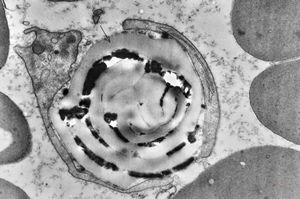

M,41y. | hairy cell leukemia - spleen - ribosome-lamella complex in tricholeukocyte